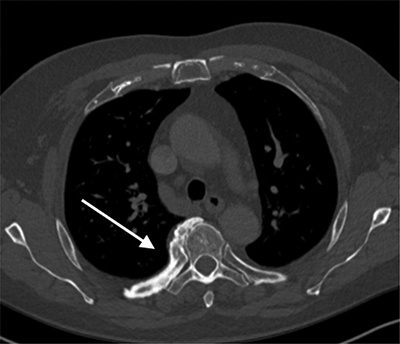

Figure 1

CT thorax axial images in bone window.